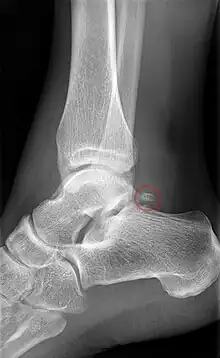

Talus injuries may be difficult to recognize,[9][10] and lateral process fractures in particular may be radiographically occult. If not recognized and managed appropriately, a talus fracture may result in complications and long-term morbidity. A 2015 review came to the conclusion that isolated talar body fractures may be more common than previously thought.[4]

A fractured talar body often has a displacement that is best visualised using CT imaging. In case a talus fracture is accompanied by a dislocation, restoration of articular and axial alignment is necessary to optimize ankle and hindfoot function.[9]

Lateral view of the human ankle, including the talus